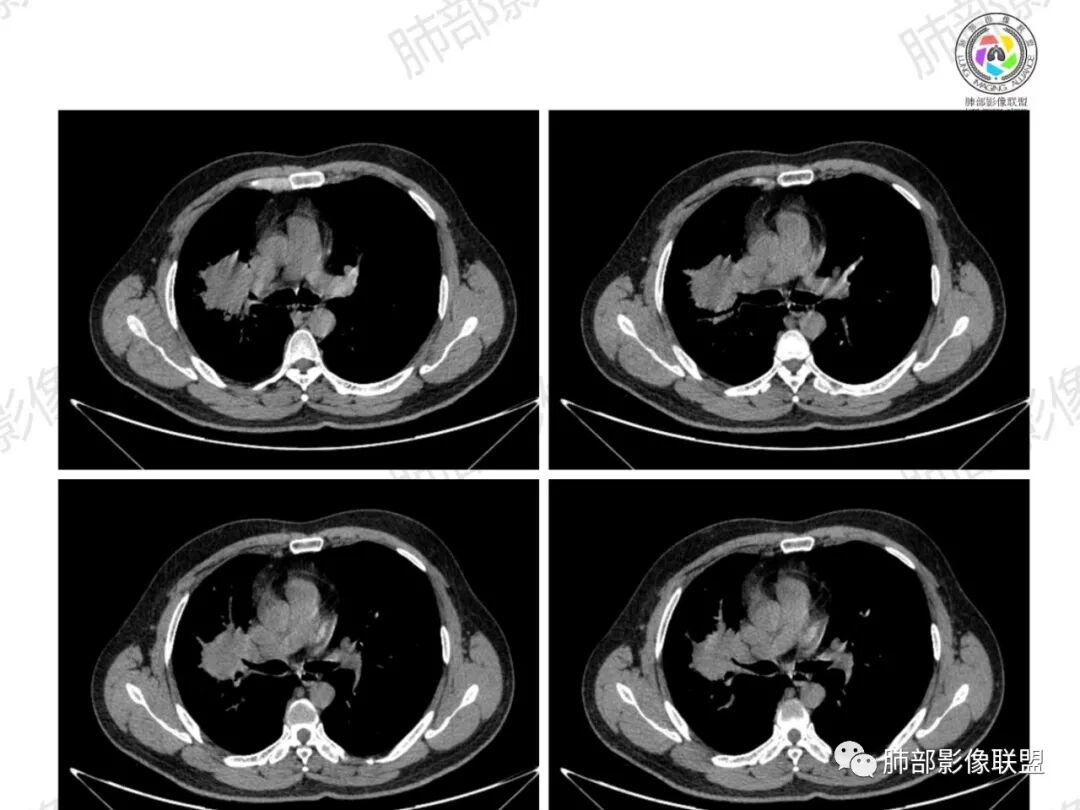

浅分叶,内部坏死部分边界不清,实性部分明显强化

环形强化

坏死区几乎是寸草不生

纵隔淋巴结肿大并不明显,就这一个肿大较明显,但仍呈椭圆形,中心少许坏死。

1、坏死区内寸草不生;2、病灶环形强化;3、远端树芽和结节;4、远端不是阻塞性炎症,而是树芽和结节,右肺上叶前后段都有,后段为主,而堵塞的支气管应该是前段;这些树芽的位置不是堵塞支气管的责任区;5、支气管不是突然截断堵塞,而是逐渐狭窄;6、纵隔淋巴结是椭圆形增大,内有坏死,不是肿瘤的圆形饱满;7、支气管周围粘液样坏死,符合仙人掌结核改变;

2、湖泊样坏死:这个病例其实不是湖泊样坏死。湖泊样坏死边界不清,周围有水草样改变;这个病例的坏死更像水库,不是湖泊,坏死区边界清楚,里面寸草不生;

水库:是人工的,边缘是石头彻的大坝(环形强化类似大坝),坝缘没草长,边界清楚。

湖泊:是天然的,周围没有环形强化的大坝,是逐渐过渡到强化区的,边缘可有细小血管或者坏死不彻底的肿瘤区。